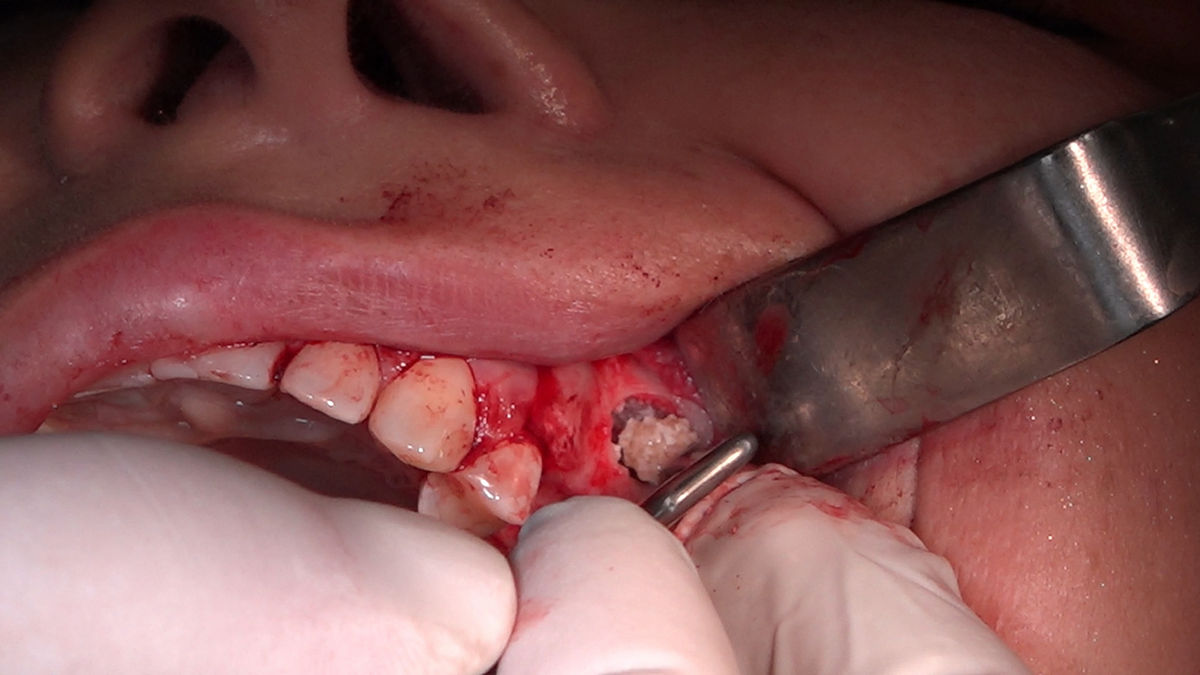

Chirurgia implantologiczna to temat wiodący 5 Sesji X Sezonu Practiculum Implantologii, która się odbyła 23-24 października 2020 roku. Bierze w nim udział 16 adeptów implantologii stomatologicznej. Zabiegi z udziałem Pacjentów jak zwykle poprzedziło omówienie i planowanie, tym bardziej, że zgodnie z planem wykonana została implantacja z wykorzystaniem szablonu chirurgicznego, który przygotowało laboratorium dentystyczne Wiligała Lab. Kursanci wykonywali szereg zabiegów implantologicznych i chirurgicznych oraz regeneracyjnych z zastosowaniem PRF, w tym sinus lift. Przeprowadzali je pod kierunkiem Lidera Umiejętności Implantologicznych dr n.med. Violetty Szycik, która wysoko oceniła wykonanie zabiegów.